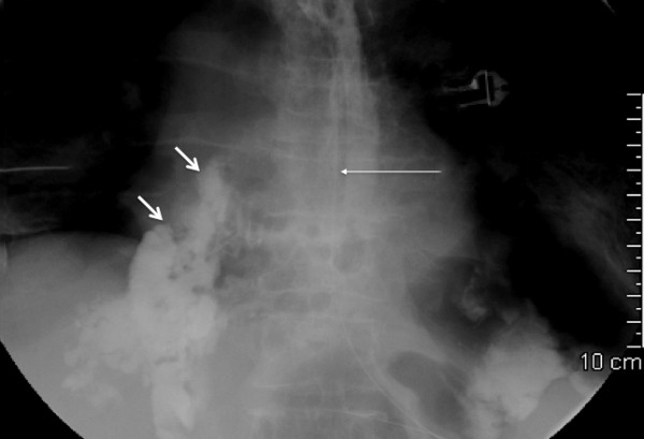

常出现恶心和呕吐。实验室检查是非特异性的,对比增强CT或血管造影

通常是必要的。阻塞性缺血通常经手术治疗,腹膜炎患者需要立即进行手术评估。图像显示的急性静脉肠系膜缺血(左)的CT扫描,显示肠壁增厚,腹腔积液,手术证实肠系膜充血(右)。肠系膜缺血与高死亡率有关(75%)。